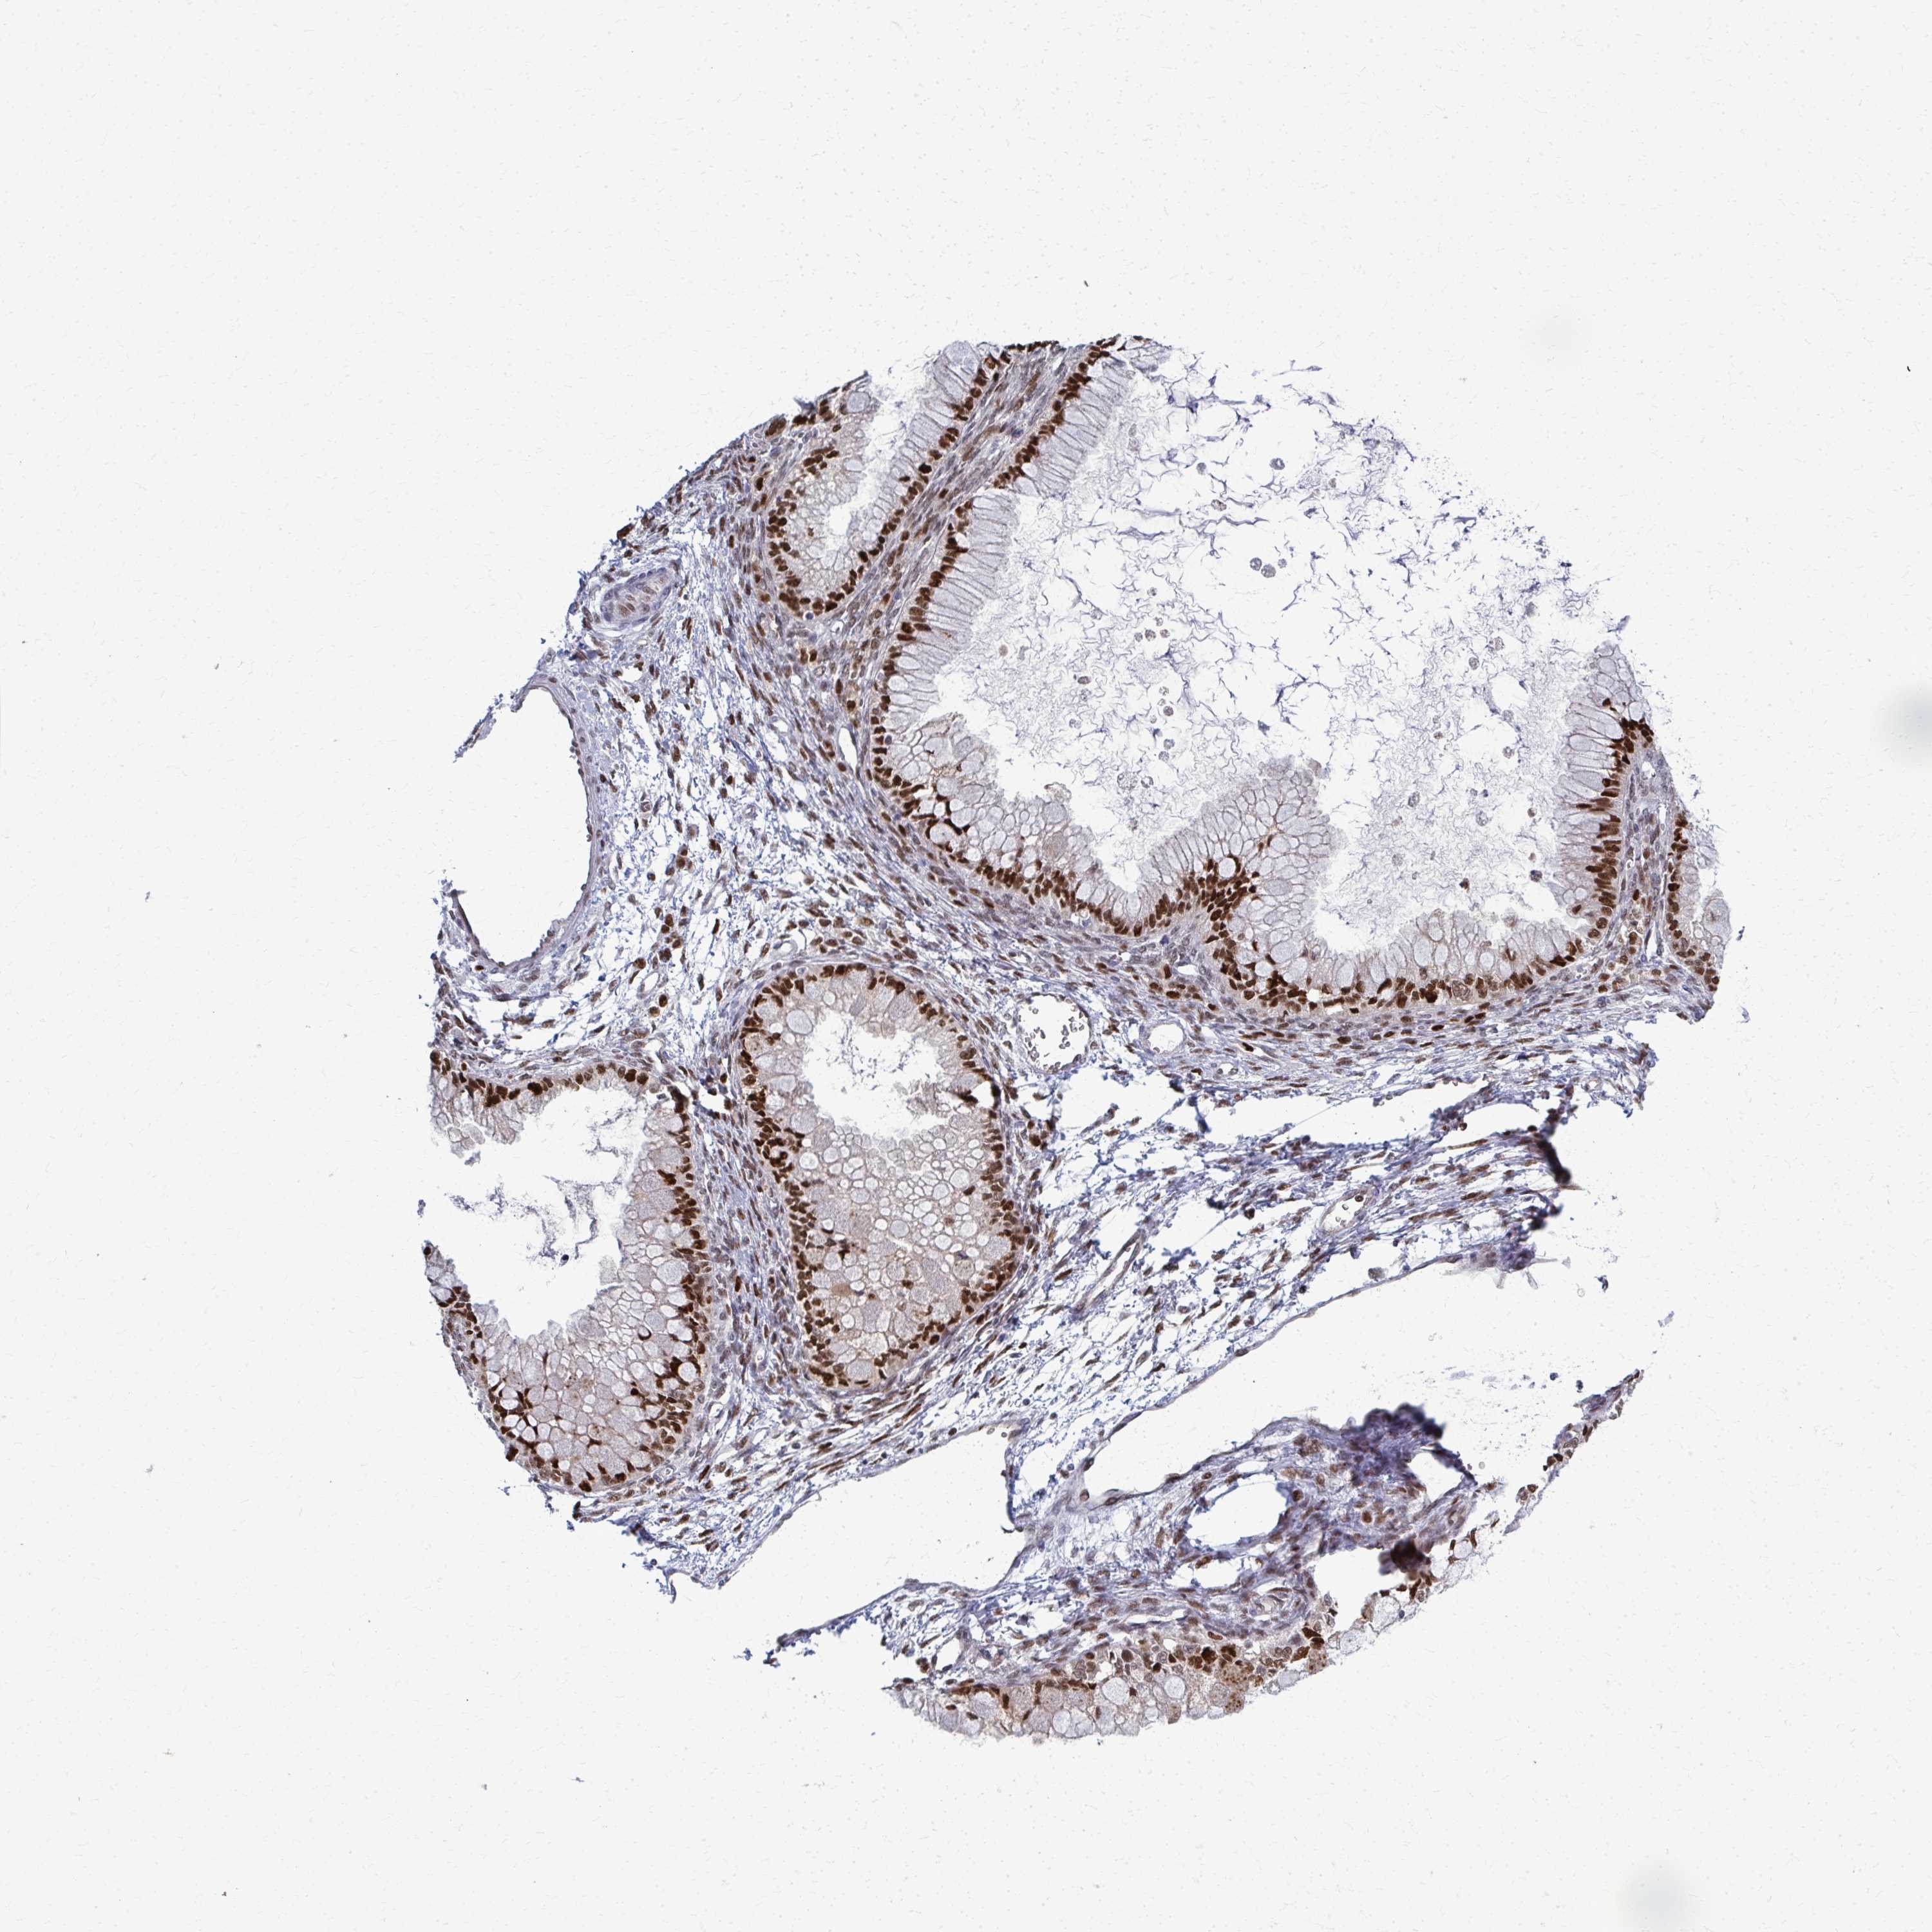

OVARIAN CANCER - Protein expressioni

A mouse-over function shows sample information and annotation data. Click on an image to view it in a full screen mode. Samples can be filtered based on level of antibody staining by selecting one or several of the following categories: high, medium, low and not detected. The assay and annotation is described here.

Note that samples used for immunohistochemistry by the Human Protein Atlas do not correspond to samples in the TCGA dataset.

Antibody stainingi

Antibody staining in the annotated cell types in the current human tissue is reported as not detected, low, medium, or high, based on conventional immunohistochemistry profiling in selected tissues. This score is based on the combination of the staining intensity and fraction of stained cells.

Each image is clickable and will lead to virtual microscopy that enables deeper exploration of all samples and also displays staining intensity scores, fraction scores and subcellular localization as well as patient and tissue information for each sample.

Antibody HPA059632

Staining

High

Medium

Low

Not detected

Intensity

Strong

Moderate

Weak

Negative

Quantity

>75%

75%-25%

<25%

None

Location

Nuclear

Cytoplasmic/membranous

Cytoplasmic/membranous,nuclear

Cystadenocarcinoma, serous, NOS

Carcinoma, NOS

Cystadenocarcinoma, mucinous, NOS

Carcinoma, endometroid